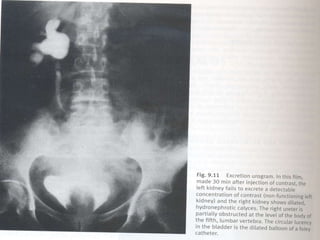

 Intravenos Urografia

Outros Analisis  Taxade Glomerular Filtracão  Microbiological Exam de Urina  Medidos Funcão Tubular Rines  Radiografia Simples  Ultrosonografia  Intravenos Urografia  Antegrade e Retrograde Urografia  Cistografia  Radionuclide Estudo  TAC e MRI  Arterorafia e Venografia